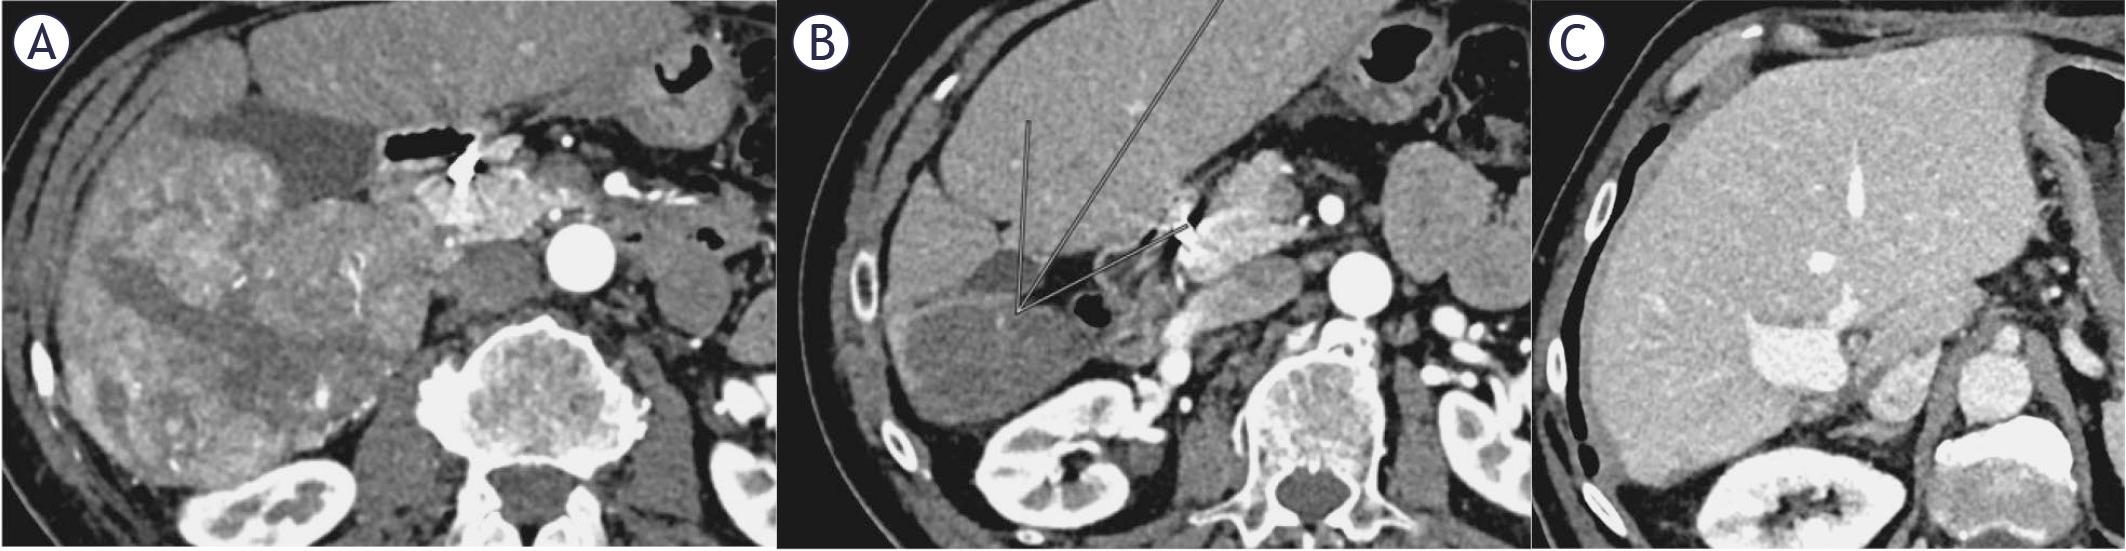

FIGURE 2.